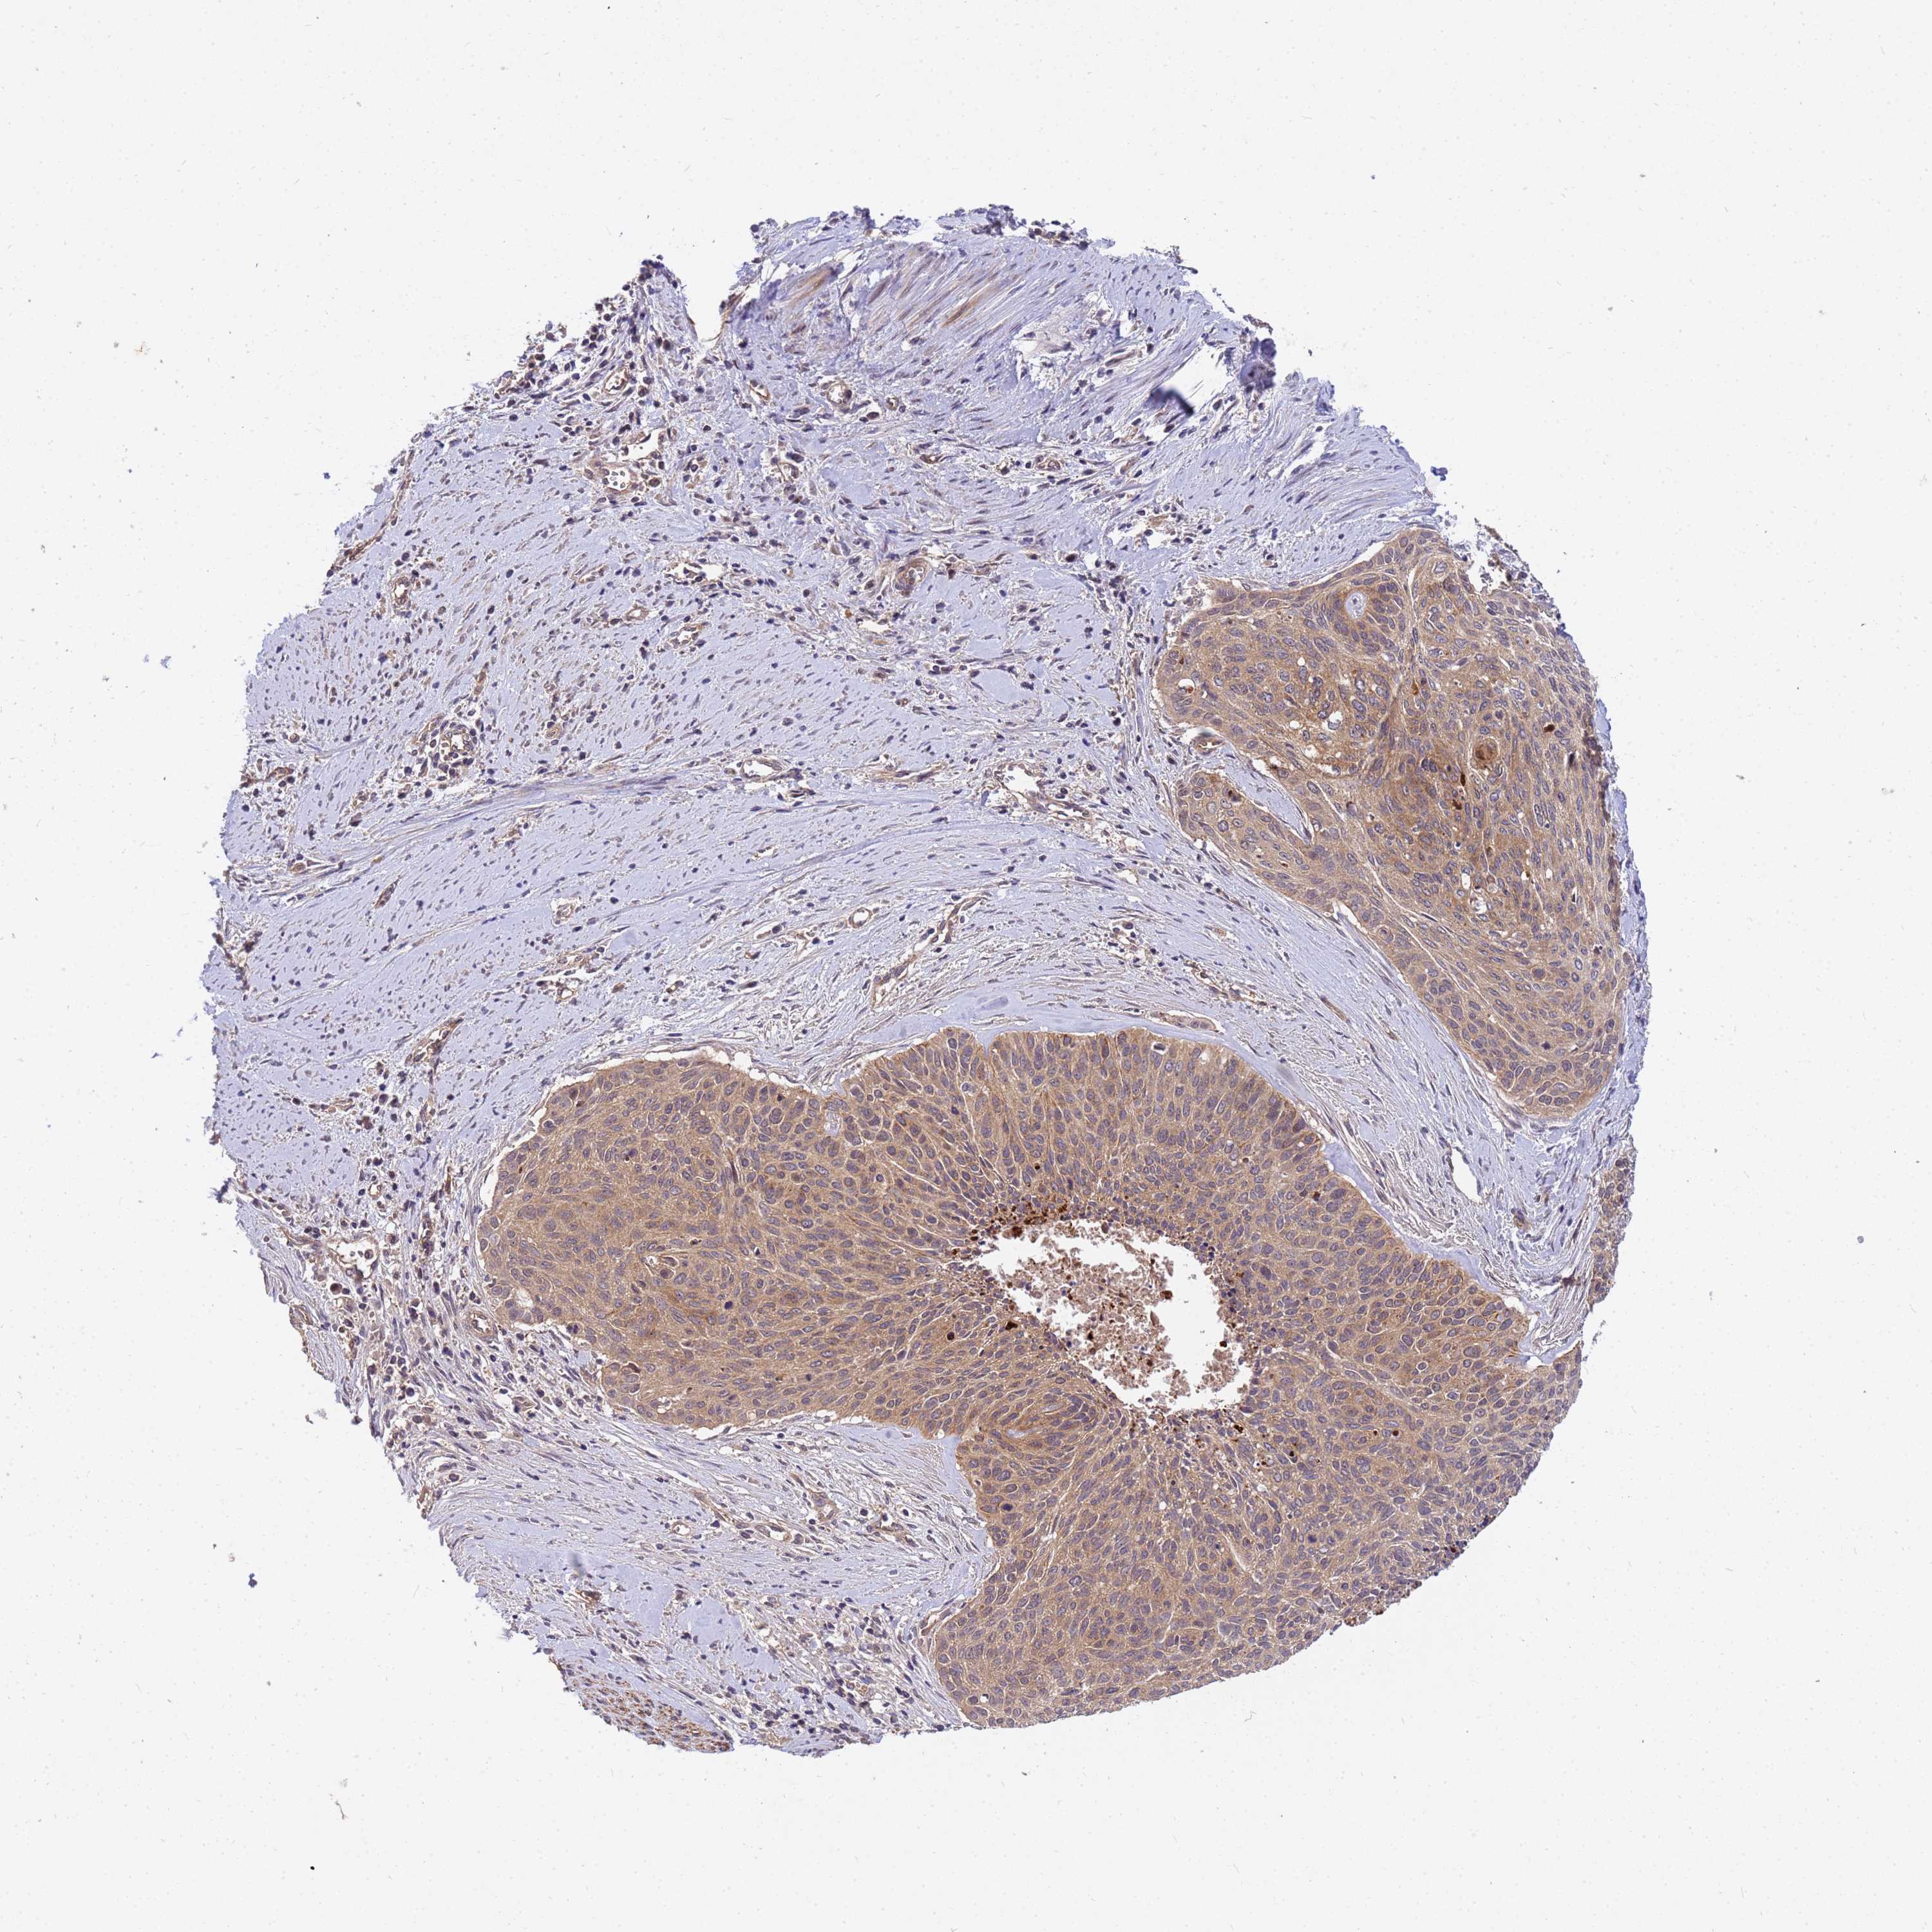

CERVICAL CANCER - Protein expressioni

A mouse-over function shows sample information and annotation data. Click on an image to view it in a full screen mode. Samples can be filtered based on level of antibody staining by selecting one or several of the following categories: high, medium, low and not detected. The assay and annotation is described here.

Note that samples used for immunohistochemistry by the Human Protein Atlas do not correspond to samples in the TCGA dataset.

Antibody stainingi

Antibody staining in the annotated cell types in the current human tissue is reported as not detected, low, medium, or high, based on conventional immunohistochemistry profiling in selected tissues. This score is based on the combination of the staining intensity and fraction of stained cells.

Each image is clickable and will lead to virtual microscopy that enables deeper exploration of all samples and also displays staining intensity scores, fraction scores and subcellular localization as well as patient and tissue information for each sample.

Antibody HPA043236

Antibody CAB003848

Squamous cell carcinoma, NOS

Adenocarcinoma, NOS